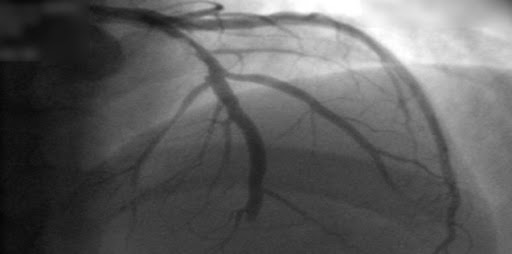

Mortalidad cardíaca en pacientes aleatorizados a revascularización coronaria electiva más terapia médica o terapia médica sola: revisión sistemática y metanálisis

21 mayo 2021

En pacientes con enfermedad coronaria estable, la aleatorización a revascularización coronaria electiva más tratamiento médico condujo a una reducción de la mortalidad cardíaca en comparación con el tratamiento médico solo. El beneficio de supervivencia cardíaca después de la revascularización mejoró con períodos de seguimiento más prolongados y se asoció con menos IAM espontáneos. Eur Heart J , 18 de mayo de 2021